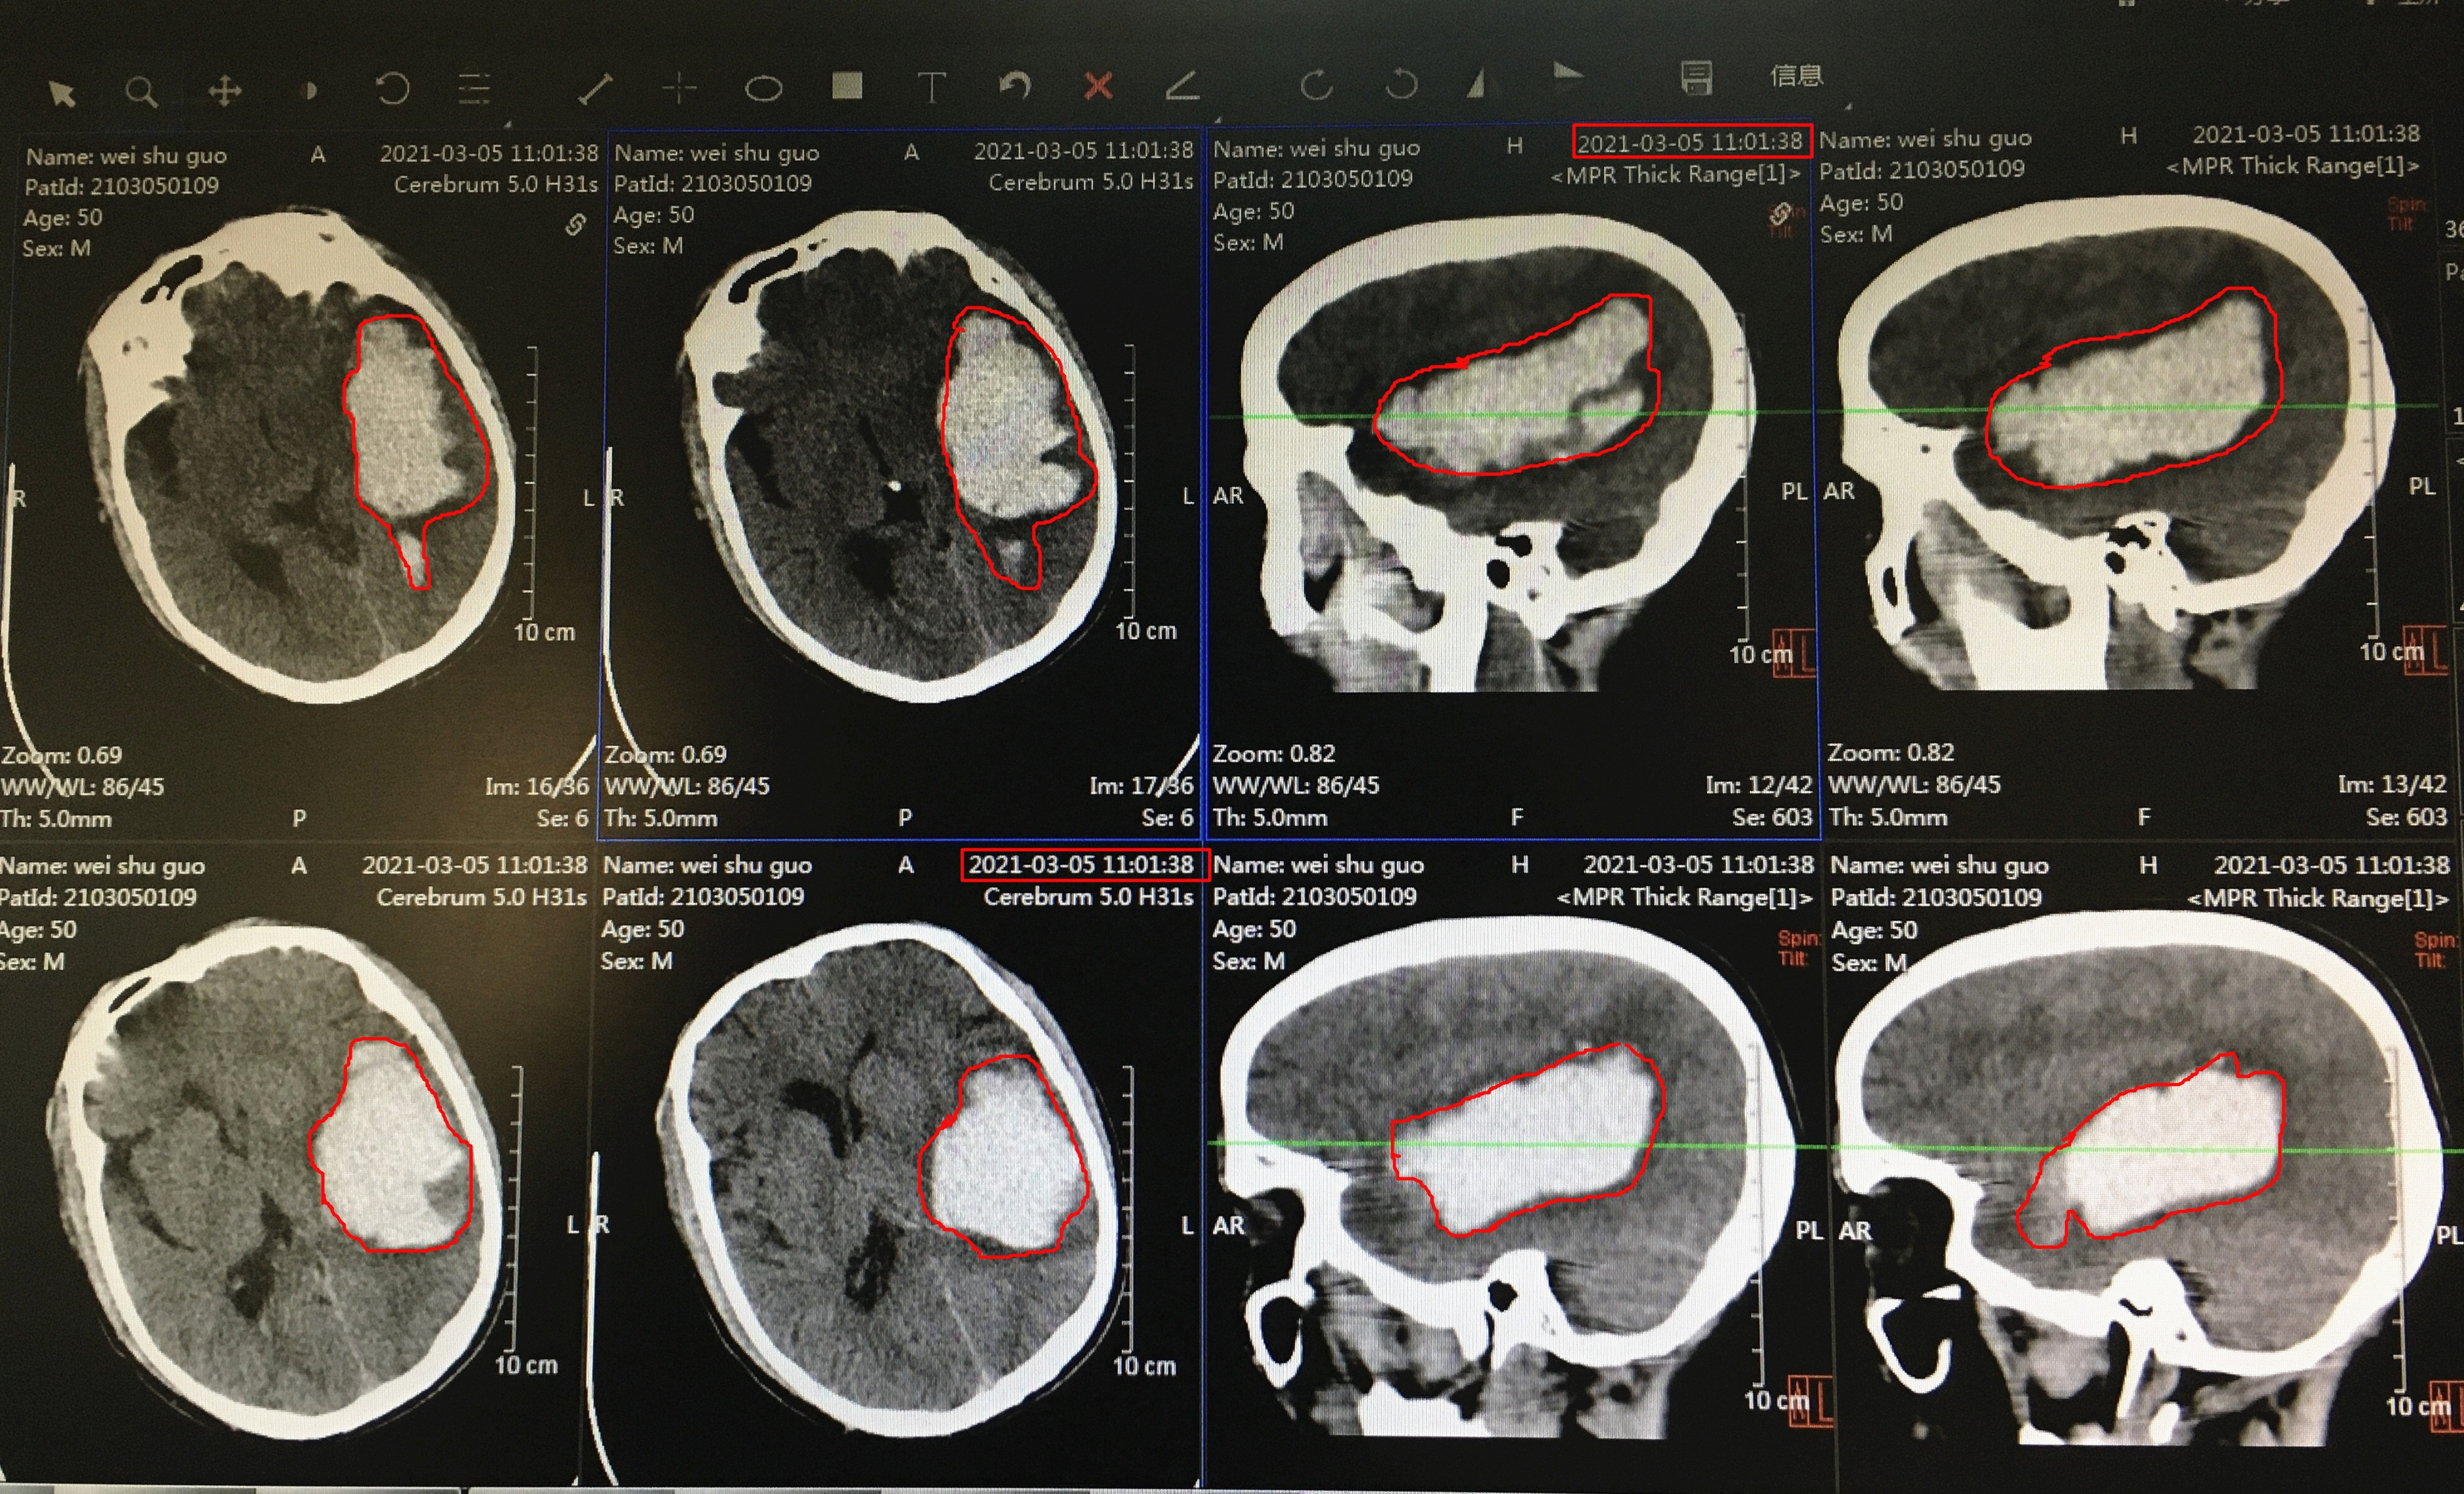

据悉,50岁的韦先生高血压病史已有十余年,一直没有到医院规范治疗。2021年3月3日中午12时许突发头痛、呕吐,伴言语不清,神志模糊,右上肢无法上提,右下肢无法站立,被家人送入我院急诊科就诊,头部CT检查结果显示左侧颞顶枕叶脑出血(量约89ml),有脑疝倾向、危及生命可能,急诊科医务人员立即护送神经外科治疗。

术前图片,白点为出血位置及范围